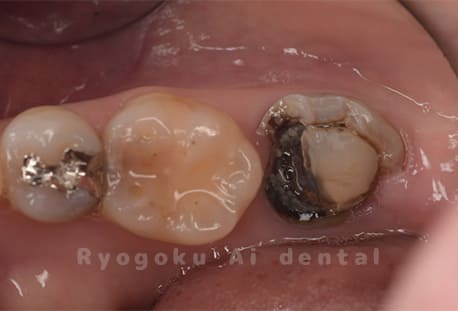

Case03

- 重度カリエス、慢性根尖性歯周炎

- 治療内容

- 自家歯牙移植

- 治療費用

- 220,000円

他院で右下の根の治療を行い、セラミックを被せる説明をされていたが、根の治療が終わらないため転院された患者さんです。隣の親知らずの抜歯の必要性と、根の治療を行なっている歯牙の予後が悪いため、移植治療を提案し、右下の親知らずの抜歯と同時に、右下の奥歯(7番)への移植治療を行いました。被せ物を行う必要もなく、順調に経過してます。

<リスク・副作用>

治療後、痛みや違和感、出血、腫れなどが出る事があります。喫煙者、糖尿病などの方の場合、歯が生着しない場合があります。